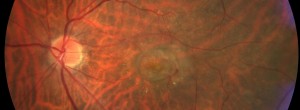

MANTRA: evaluación de la asociación entre la sensibilidad y el flujo retiniano en la DMAE

Ensayo clínico OAKS-DERBY: Eficacia y seguridad de pegcetacoplan en el tratamiento de la atrofia geográfica secundaria a DMAE

Ensayo clínico TALON: Eficacia y seguridad de brolacizumab en el tratamiento de la DMAE exudativa

Ensayo clínico LUCERNE: Eficacia y seguridad de FARICIMAB respecto de aflibercept en el tratamiento de la degeneración macular asociada a la edad exudativa